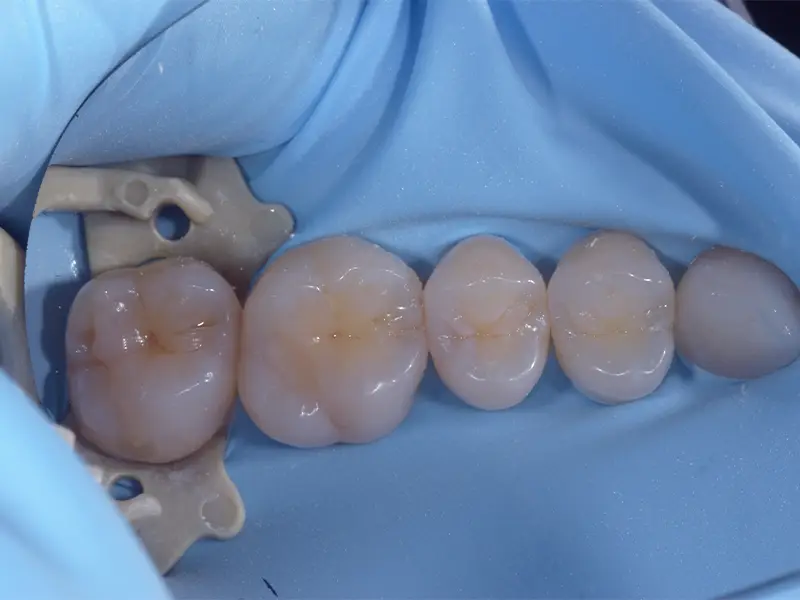

Dopo la diagnosi e la rimozione del tessuto danneggiato, il dente viene ricostruito con materiali compositi estetici di ultima generazione. Utilizziamo la diga di gomma per isolare il campo operatorio e garantire una sigillatura ottimale.

Il trattamento è completamente indolore e, una volta completato, il dente recupera pienamente solidità, funzione masticatoria e integrità strutturale. Il restauro sarà inoltre del tutto invisibile!

L’obiettivo è un restauro duraturo, invisibile e perfettamente integrato con il resto della dentatura.

- Utilizzo della diga di gomma per sicurezza e precisione